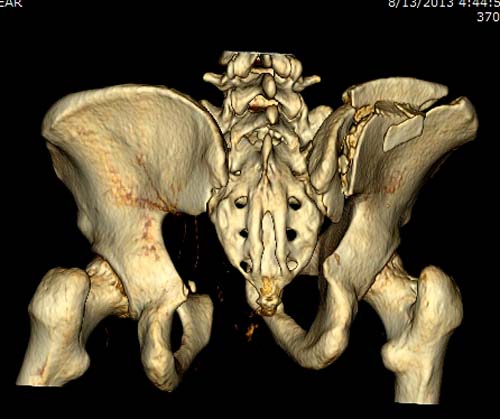

До операции желательно выставить все стандартные снимки: обзорный таза,

вход + выход. А популярный у всех 3Д используется только для общего

обзора, но не для детального изучения. Обычно КТ“для

диагностики-стандарт, а послеоперационно - дополнительный расход”. Лучше

обычные рентген-снимки, но бывают исключения, когда на снимке имеются

неясности, например, винт через сакральный форамен или через сустав!